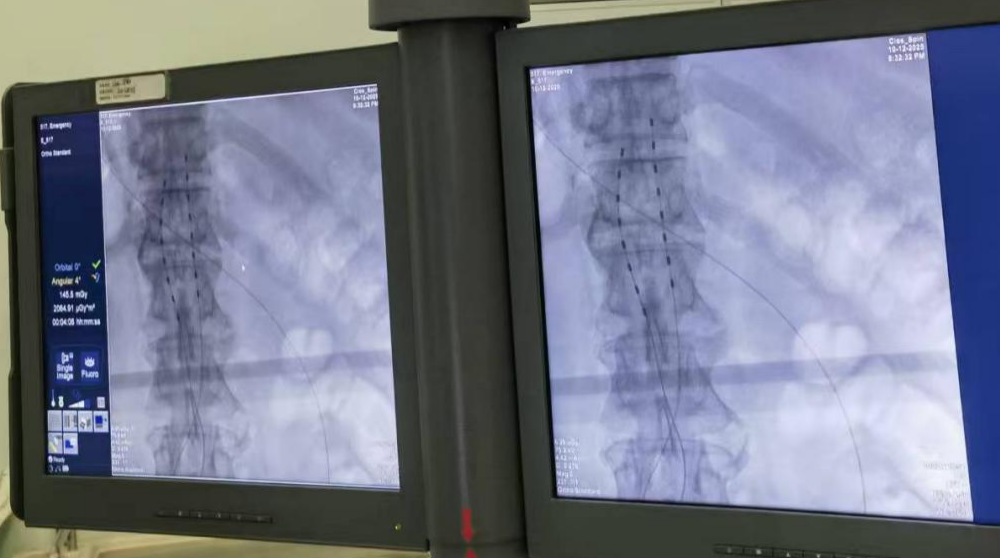

Two 8-contact needle electrodes were used for spinal cord stimulation and implanted in the T11-L1 segment. The location of the electrode implantation target was confirmed during the operation by combining imaging and the patient's subjective description.

Intraoperative electrode imaging